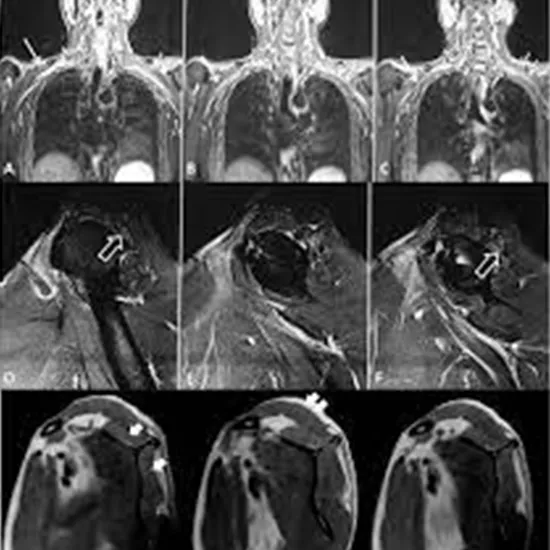

MRI Screening Right Parascapular is an imaging procedure used to create a detailed picture of the structure of the right parascapular and its surrounding tissues using a strong magnetic field.  This scan is performed to evaluate the scapula which is the largest bone in the shoulder region for muscle tear, muscle injury, ligament tear, scapula fracture, soft tissue injuries, etc.